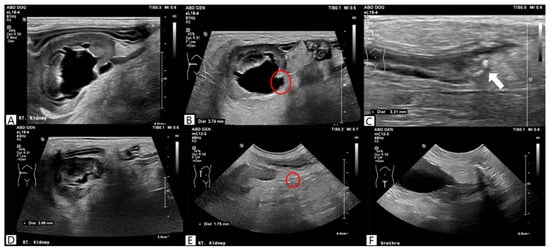

No remarkable abnormalities were observed on thoracic radiography. Abdominal radiography performed in the right lateral and ventrodorsal projections showed decreased serosal detail, gastric gas dilation, and an irregular margin in the left kidney, whereas the right kidney was poorly visualized. No radiopaque uroliths were identified on radiography. Abdominal ultrasonography was performed using an ultrasound system (Philips EPIQ 7®, Philips Healthcare, Andover, MA, USA) equipped with a linear array transducer (EL18-4, Philips Healthcare, Andover, MA, USA; 2–22 MHz), revealing a hyperechoic peritoneum and irregular kidney margins. Notably, the right kidney exhibited marked dilation of the renal pelvis (14.2 mm) and proximal ureteral dilation (maximum, 3 mm) without evidence of calculi. Differential diagnoses for hydronephrosis included pyelonephritis, ureteral stenosis, ureteral obstruction, and an ectopic ureter. Pyelonephritis was considered the most likely condition in the absence of identifiable calculi. Initial treatment included empirical antibiotic therapy with ampicillin-sulbactam (Sulbacin®, Shinpoong Pharmaceutical Co., Seoul, Republic of Korea; 20 mg/kg, intravenously, three times daily) and enrofloxacin (Baytril®, Elanco Animal Health Incorporated, Greenfield, IN, USA; 3 mg/kg, subcutaneously, twice daily), analgesia with lidocaine (Daihan Lidocaine HCL Hydrate®, Daehan Pharmaceutical Co., Seoul, Republic of Korea; 1 mg/kg/h)—ketamine (Hanall Ketamine HCL®, HanAll Biopharma Co., Seoul, Republic of Korea; 0.2 mg/kg/h) continuous rate infusion. Because the D-dimer level was markedly elevated, dalteparin (Fragmin®, Pfizer, Puurs, Belgium; 150 IU /kg, subcutaneously, three times daily) was administered prophylactically to reduce thromboembolic risk. Fluid therapy with lactated Ringer’s solution (Hartmann’s solution®, JW Pharmaceutical, Gwacheon, Republic of Korea) was administered to correct 7% dehydration for 6 h. Once hydration improved and the target body weight was achieved, the infusion rate was reduced to the maintenance fluid rate, which was continued until discharge. On day 4 of hospitalization, ultrasonography showed worsening dilation of the right renal pelvis (16.1 mm) and ureteral dilation (3.74 mm), with distal ureteroliths (maximum diameter, 3.31 mm), as shown in Figure 2.

Figure 2. Ultrasonographic findings on day 4 revealed severe dilation of the right renal pelvis (A), distention of the right ureter (red circle) (B), and the presence of ureteral calculi (white arrow) (C).